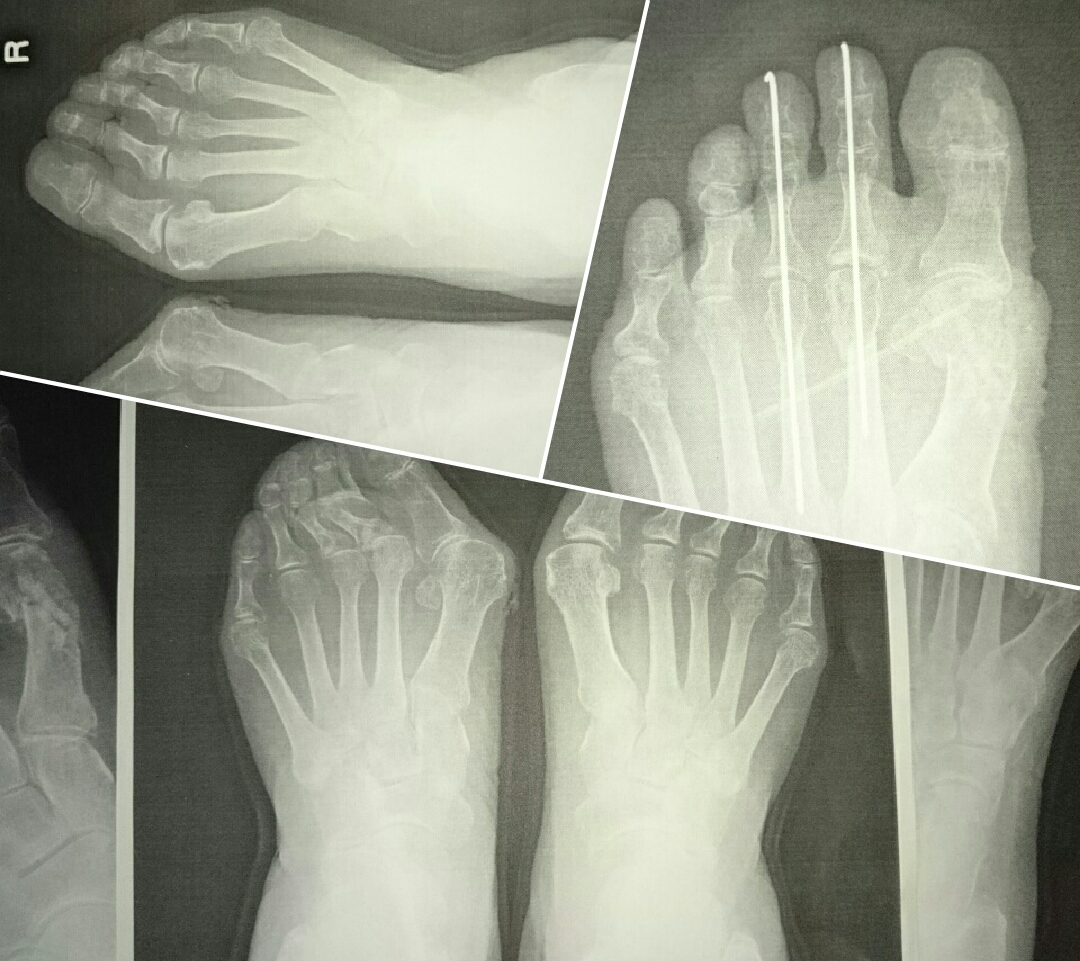

右のレントゲン画像は外反母趾手術をされ、

医療で保険適用の靴、インソールを使いましたが具合が・・・

その結果、足に合う靴をご依頼いただいたお客様。

このレントゲン写真のお客様の現在までの経緯

外反母趾手術・お役様の経過